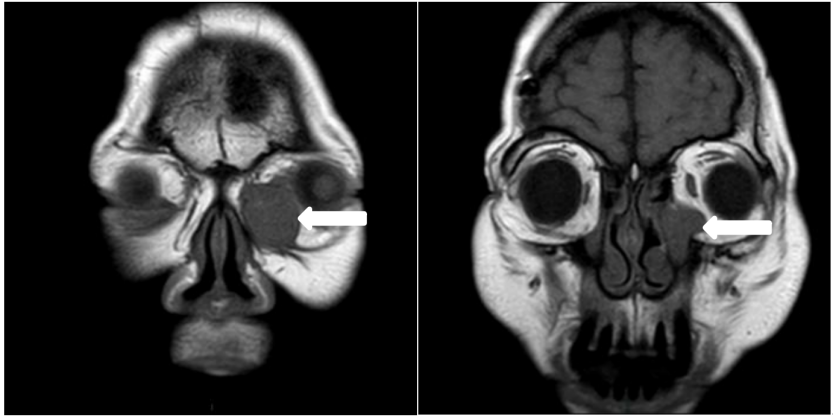

患者女,62岁,因左眼内眦肿胀1年于2024年8月19日入院。体格检查:左眼内眦部下方隆起,扪及直径约1.6 cm×1.8 cm的包块,质硬,轻微压痛,肿物自泪囊窝处向眶内延续。泪道冲洗:右眼上下泪小管内冲水通畅。左眼下泪小管冲水少量入咽,大部原路返流;上泪小管冲水全部原路反流,不能探入泪囊。眼眶彩色多普勒超声(彩超)检查(图1):左眼泪囊区可见低回声区,范围约2.4 cm×2.2 cm×1.8 cm,边界清,内回声欠均匀。彩色多普勒血流显像(color doppler flow imaging, CDFI):内可见树枝样较丰富血流信号。眼眶计算机断层扫描(computed tomography, CT)检查(图2):1)左侧泪囊鼻泪管及下鼻道内异常密度影,考虑肿瘤性病变可能大;2)左侧骨性鼻泪管增宽。眼眶磁共振成像(magnetic resonance imaging, MRI)检查(图3)示左侧泪囊鼻泪管及下鼻道内异常信号,考虑肿瘤性病变可能大。实验室检查结果未见明显异常。于2024年8月20日在全身麻醉下经皮肤切口联合鼻内镜入路行左眼眶泪道肿物切除术,先自内眦部肿物表面皮肤做切口,见肿物有完整致密薄膜,呈灰白色,向泪囊窝内延续;转至鼻内镜下,自泪颌缝前约6~7 mm纵向切开鼻黏膜向下切至下鼻甲黏膜,向后剥离鼻黏膜,暴露上颌骨额突及下鼻甲,使用咬骨钳及动力磨钻去除骨性鼻泪管内侧壁,见泪囊、鼻泪管膨大,将泪囊、鼻泪管连同鼻泪管口附近部分下鼻甲、下鼻道黏膜充分游离,其间见鼻泪管受挤压后鼻泪管口有不规则的灰白色软性颗粒样物质溢出;经内眦切口将肿物摘除。将鼻黏膜复位覆盖创面,可降解止血棉填塞固定鼻黏膜,分层缝合内眦切口。标本巨检:病变累及泪囊、鼻泪管全长,大小约为3.5 cm×2.5 cm×1.6 cm,外壁呈灰白色,有较厚的包膜结构,局部切开可见内含大量白色质软胶冻状的不规则颗粒样、乳头样结构;病理诊断(图4):(左眼泪囊部)上皮源性肿瘤,囊性结构,衬覆柱状上皮、鳞状样上皮,伴有乳头状结构,可见少量黏液细胞。CK7(部分+)、CK5/6(+)、S-100(少量+)、P63(+)、SOX10(少量+)、Ki-67阳性细胞数约2%、PAS染色(少量+)。结合组织学形态及免疫组化结果,符合泪囊导管囊性扩张伴鳞状细胞化生,伴乳头状瘤形成,伴少量黏液细胞化生。患者术后3周时复诊见鼻黏膜基本愈合,出院后曾到耳鼻喉科会诊建议观察随诊;2024年11月2日第二次复诊见左侧鼻腔黏膜愈合好,未见复发改变(图5),患者除溢泪症状,无其他不适。下一步诊疗计划:定期复诊,术后6个月以上无复发可考虑行使用鼻黏膜再造泪道的结膜-鼻腔吻合置管术。

图 1 一例泪道乳头状瘤的彩超结果

Figure 1 Color doppler ultrasonography results of a case of lacrimal papilloma

左眼泪囊区可见低回声区,范围约2.4 cm×2.2 cm×1.8 cm,边界清,内回声欠均匀。彩色多普勒血流显像:内可见树枝样较丰富血流信号。A hypoechoic area is visible in the left lacrimal sac region, measuring approximately 2.4 cm × 2.2 cm × 1.8 cm, with clear borders and uneven internal echoes. Color Doppler flow imaging reveals a rich, branching pattern of blood flow signals within the area.